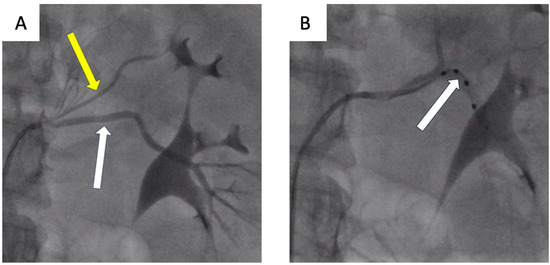

- Możeńska, O.; Rosiak, M.; Gziut, A.; Gil, R.J.; Kosior, D.A. First-in-man experience with renal denervation of multiple renal arteries in a patient with solitary kidney and resistant hypertension. Pol. Arch. Intern. Med. 2017, 127, 60–62. [Google Scholar] [CrossRef]

- Atas, H.; Durmus, E.; Sunbul, M.; Mutlu, B. Successful accessory renal artery denervation in a patient with resistant hypertension. Heart Views 2014, 15, 19–21. [Google Scholar] [PubMed]

- Bertoldi, L.; Latib, A.; Piraino, D.; Regazzoli, D.; Sticchi, A.; Pizzetti, G.; Camici, P.G.; Colombo, A. Renal denervation in a patient with two renal accessory arteries: A case report. Blood Press 2013, 22, 325–328. [Google Scholar] [CrossRef] [PubMed]

- de Leon-Martinez, E.P.; Garza, J.A.; Azpiri-Lopez, J.R.; Dillon, K.N.; Salazar, L.O.; Canepa-Campos, F.; Rousselle, S.D.; Tellez, A. Safety and Clinical Outcome of the Delivery of Radiofrequency Nerve Ablation Therapy in a Renal Artery of Unusual Anatomy. High Blood Press Cardiovasc. Prev. 2015, 22, 445–448. [Google Scholar] [CrossRef]